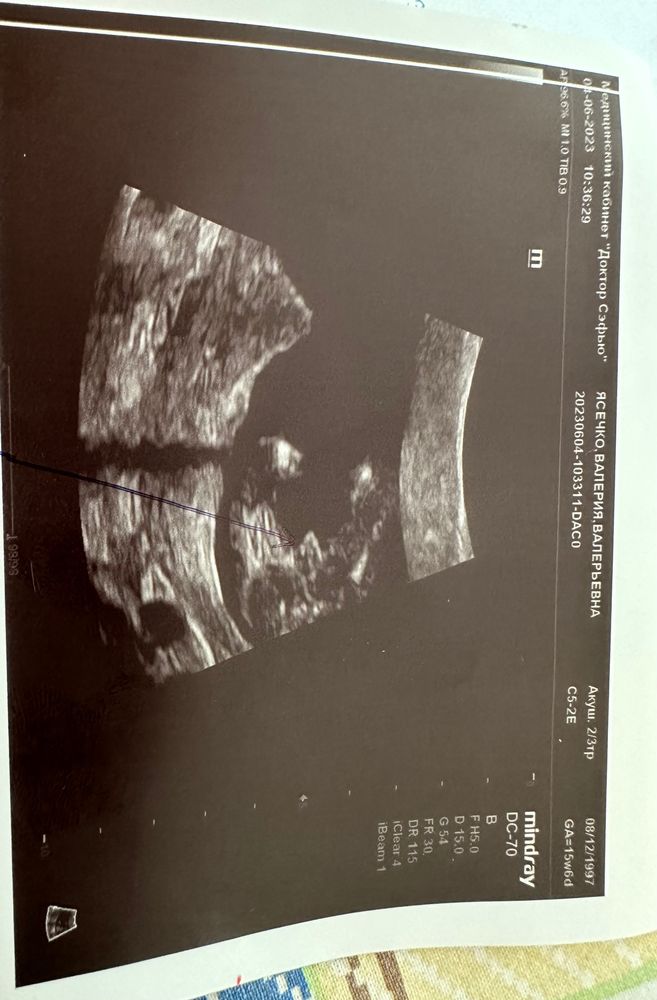

Сказали что это девочка ,а это пуповина , мне одной кажется что это пацан

С этого ракурса и на этом снимке я бы сказала мальчик.Но врач скорее всего смотрел с разных ракурсов.возможно ему виднее

Вообще не похоже на пуповину. Как по мне - мальчик, но врачу виднее, конечно.

Мария , в 16 недель хороший узист уже всё, что надо увидит🤔

Переделайте интереса ради у другого😅